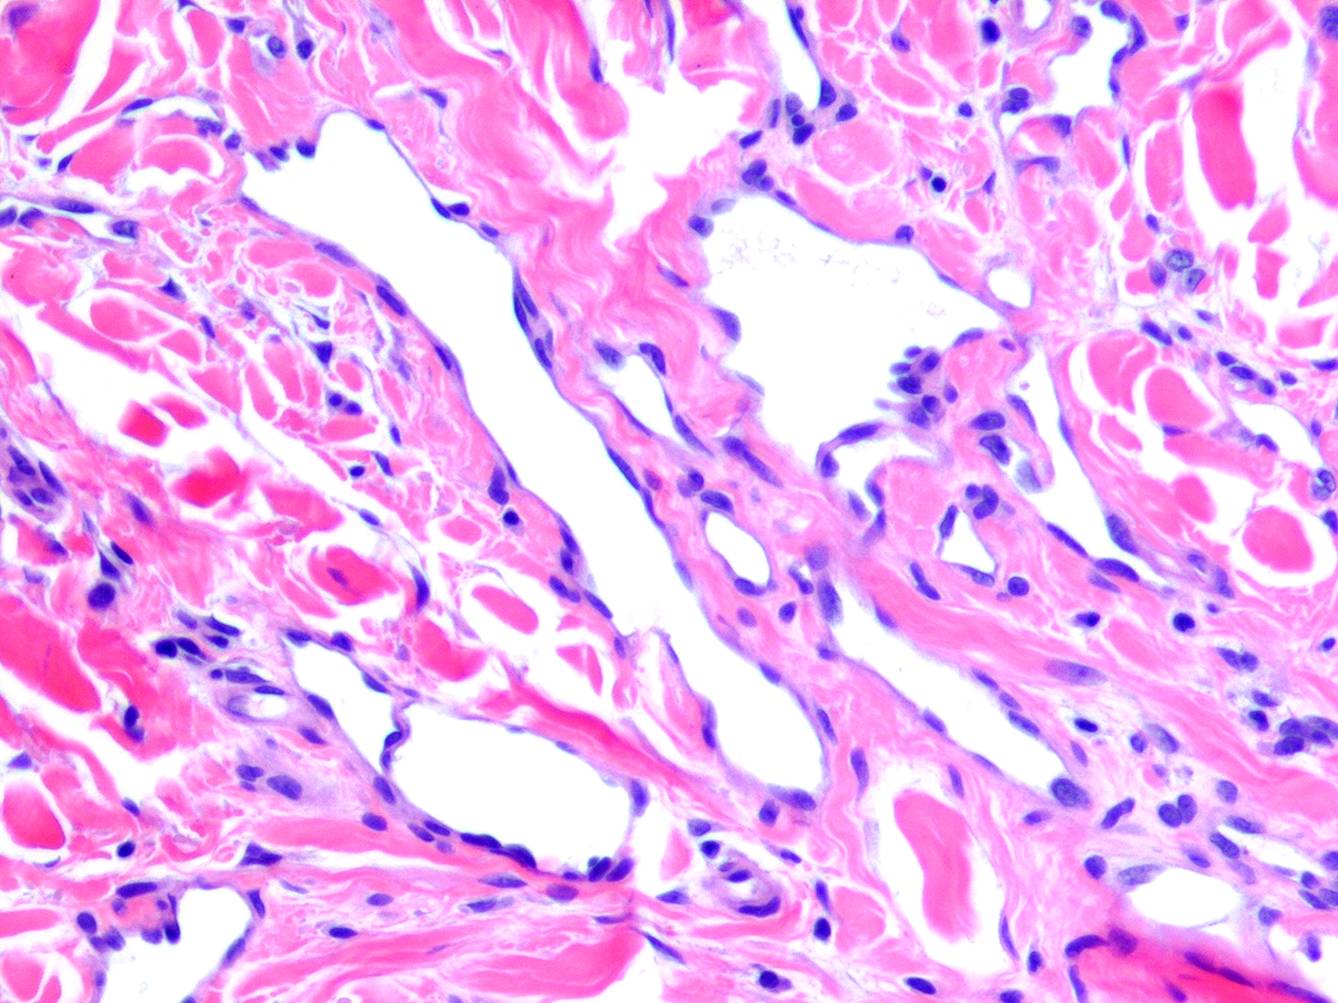

Acquired progressive lymphangioma =الورم الوعائي اللمفاوي المترقي المكتسب